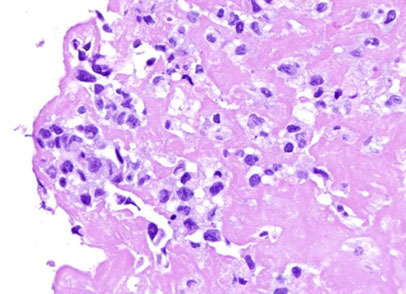

Cutaneous lymphoid hyperplasia in a 72-year-old man who presented with several purple-brown plaques on his cheeks and temples. A, The nodular infiltrate extends through the dermis with sparring of the overlying epidermis. B, It is characterized by scattered follicles with well-defined, reactive-appearing germinal centers, some of which have surrounding mantle zones. Many CD20-positive B cells are in the reactive follicles (C), and more numerous CD3-positive small T cells are present in the interfollicular areas (D). B-cell clonality studies (not shown) were negative for a clonal IGH or IGK gene rearrangement. [19]